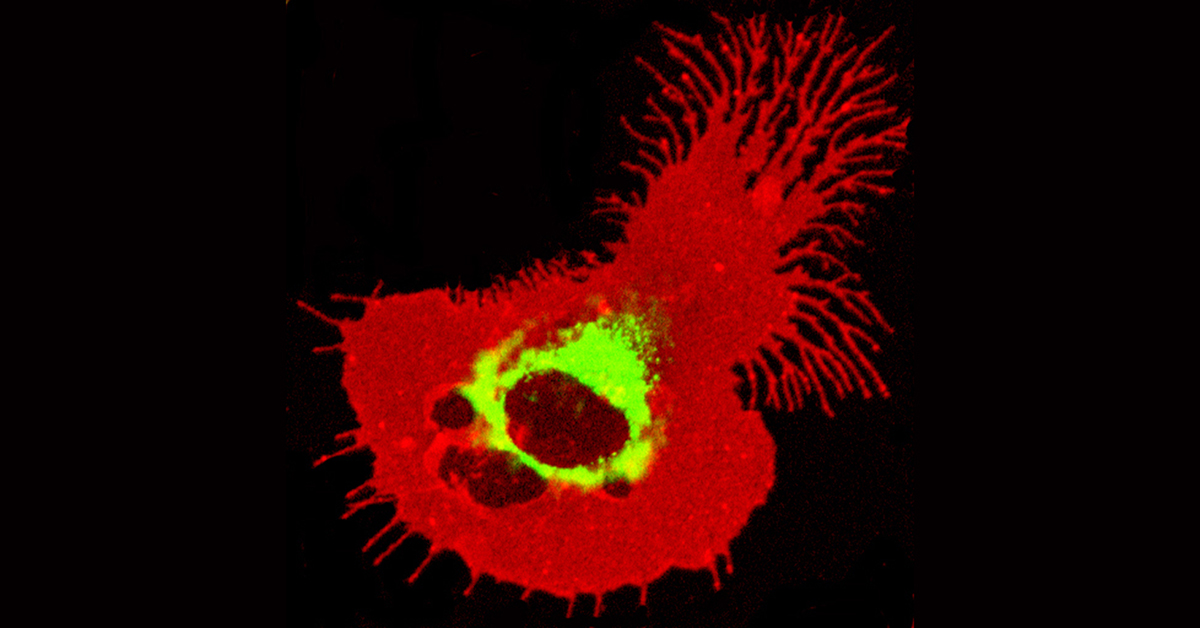

Dendritic cells. Image courtesy of WEHI.

Dendritic cells are immune cells that activate ‘killer’ T cells, which are vital for clearing viral infections, such as COVID-19, but also for triggering a response to cancers such as melanoma and bowel cancer.